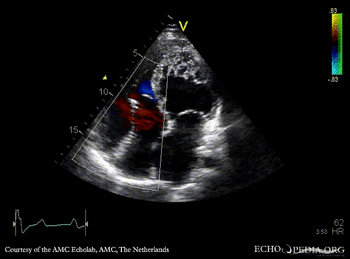

Ebstein anomaly and non-compaction cardiomyopathy

A4CH: high insertion of tricuspid valve, dilated right atrium and right ventricle, non-compaction of left ventricle A4CH with Color Doppler: severe tricuspid regurgitation